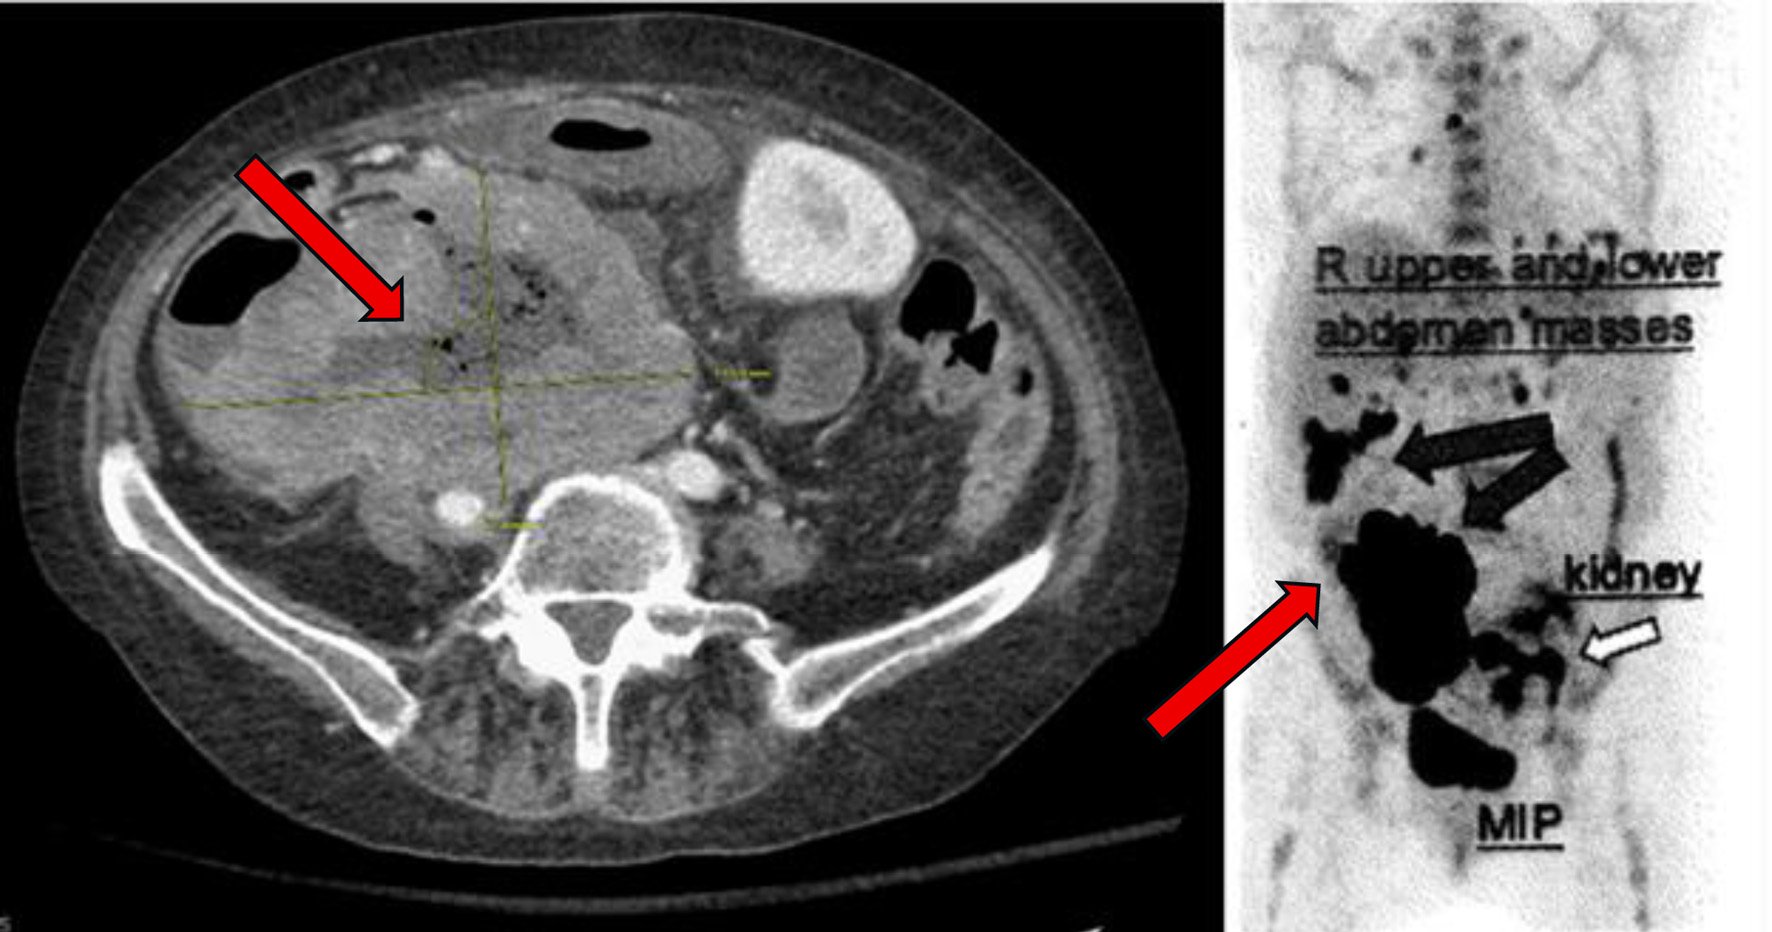

A month later, polatuzumab vedotin was added to her glofitamab and obinutuzumab as part of her treatment plan. Shortly thereafter, she was hospitalized for C. difficile colitis and abdominal pain. CT imaging revealed new ascites and further disease progression, including increased intra-abdominal tumor burden with measurements of a tumor measuring 6.5 × 9.1 cm a month prior, now progressing to 7.9 × 11.9 cm. An additional PET CT was performed a month later, which showed further disease progression (Fig. 4). Therefore, it was recommended to start the patient on glofitamab and loncastuximab tesirine-lpyl based on the LOTIS-7 trial.

Figure 4. PET scan with diffuse disease progression (arrows) 14 months after initial presentation. PET: positron emission tomography.